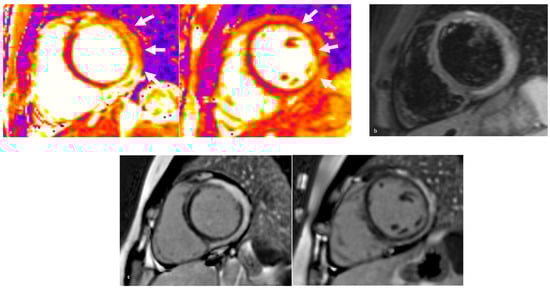

4.1. Sarcoidosis

4.1.2. Diagnostics